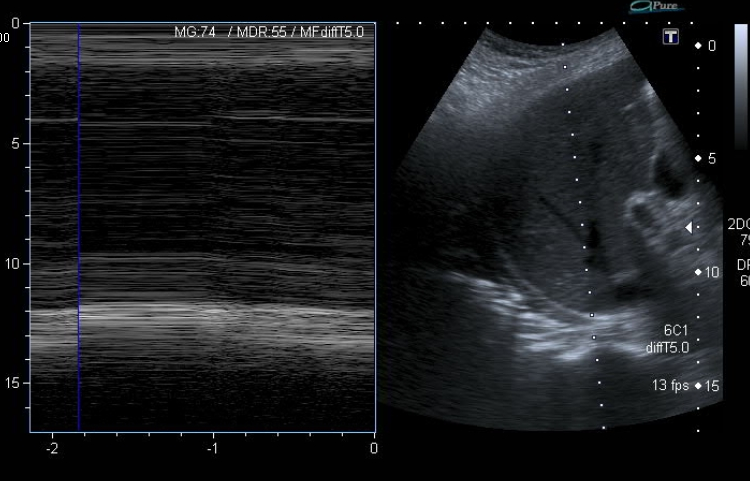

Radiografía de tórax: pérdida de volumen pulmonar con elevación de hemidiafragma derecho (imagen 1), no presente en previas (imagen 2). No claros infiltrados ni derrame pleural.